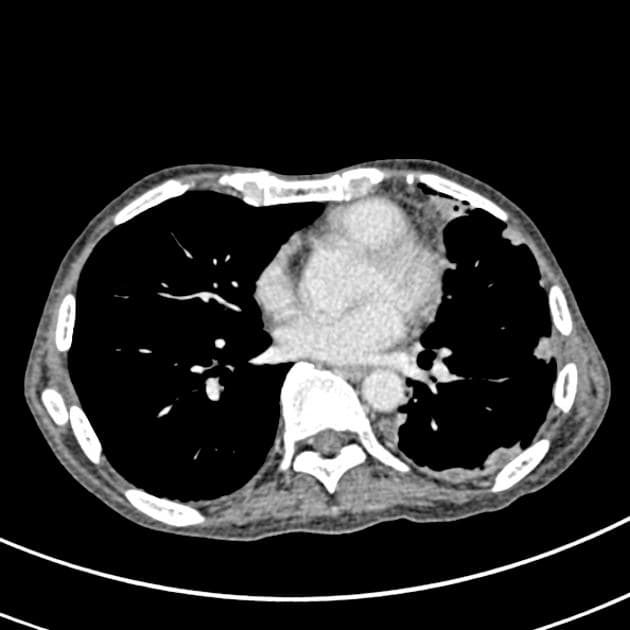

Axial non-contrast

Có một khối chứa mỡ (fat-containing mass) vùng quanh thận và thận trái, tỷ trọng hỗn hợp (mixed density), không đều (irregular), giới hạn không rõ (ill-defined). Nguồn gốc có vẻ từ cực trên/giữa thận trái phía trước, với khuyết hình chêm (wedge defect) và giảm thể tích (volume loss). Có vôi hóa dạng chấm (punctate calcification). Thấy rõ nhánh động mạch thận trái cấp máu (renal arterial branch supply) và tĩnh mạch thận trái dẫn lưu (renal venous drainage). Tổn thương ngấm thuốc không đồng nhất (heterogeneous enhancement) gợi ý u cơ mỡ mạch thận (renal angiomyolipoma) trái. Tuyến thượng thận (adrenal gland) trái bình thường.

Exophytic renal angiomyolipoma